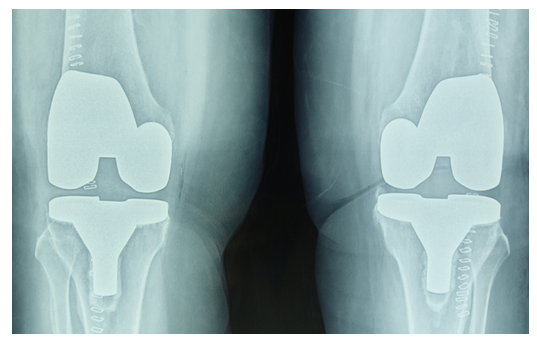

| Figure 3. The same patient after TKE (Total knee arthroplasty) |